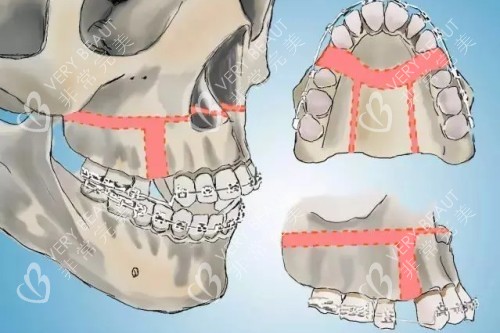

3D导板技术发明人:自主研发的“普式导板正颌术”将截骨误差控制在0.1毫米以内,这项技术已被纳入国境内颌面外科医师培训教材。

智能化术前设计:通过CT扫描获取患者颌面数据,运用3D智能系统重建三维模型,提前模拟术后结果。

术中“零误差”操作:定制的3D截骨导板可精密定位截骨线,避免损伤神经和血管。